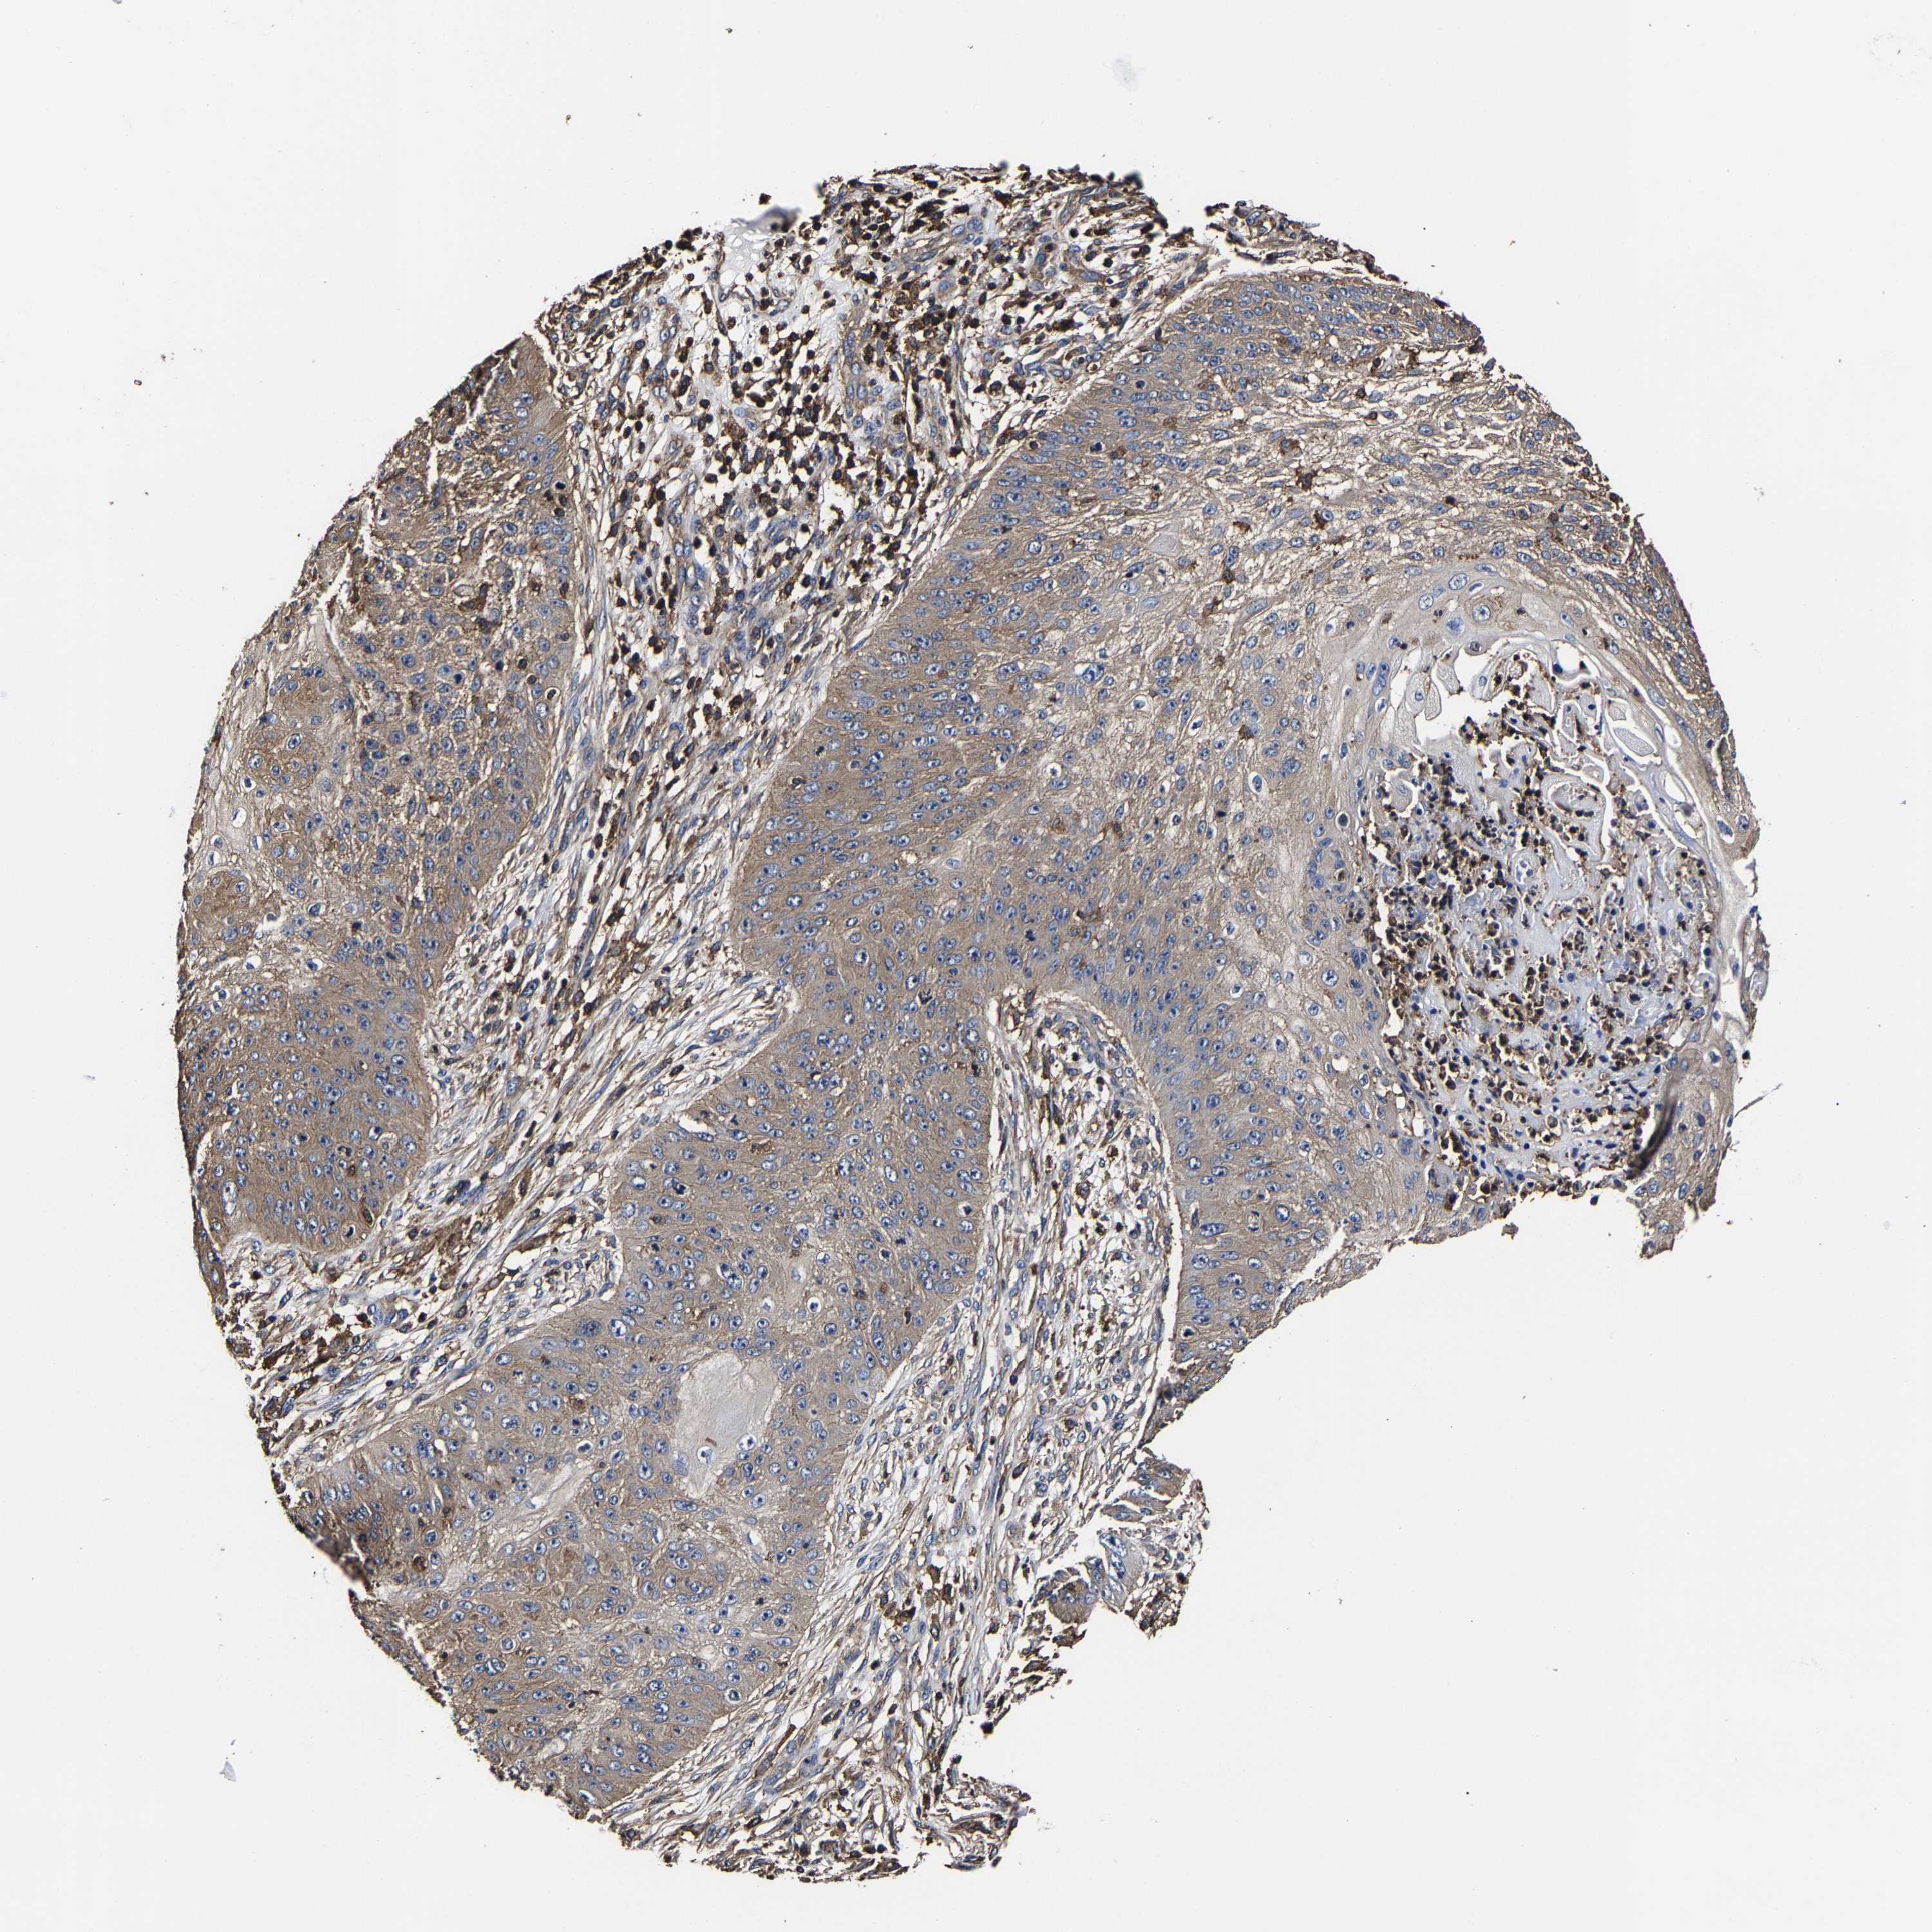

SKIN CANCER - Protein expressioni

A mouse-over function shows sample information and annotation data. Click on an image to view it in a full screen mode. Samples can be filtered based on level of antibody staining by selecting one or several of the following categories: high, medium, low and not detected. The assay and annotation is described here.

Antibody stainingi

Antibody staining in the annotated cell types in the current human tissue is reported as not detected, low, medium, or high, based on conventional immunohistochemistry profiling in selected tissues. This score is based on the combination of the staining intensity and fraction of stained cells.

Each image is clickable and will lead to virtual microscopy that enables deeper exploration of all samples and also displays staining intensity scores, fraction scores and subcellular localization as well as patient and tissue information for each sample.

Antibody HPA019957

Staining

High

Medium

Low

Not detected

Intensity

Strong

Moderate

Weak

Negative

Quantity

>75%

75%-25%

<25%

None

Location

Nuclear

Cytoplasmic/membranous

Cytoplasmic/membranous,nuclear

Squamous cell carcinoma in situ, NOS

Squamous cell carcinoma, NOS

Squamous cell carcinoma, metastatic, NOS

Basal cell carcinoma